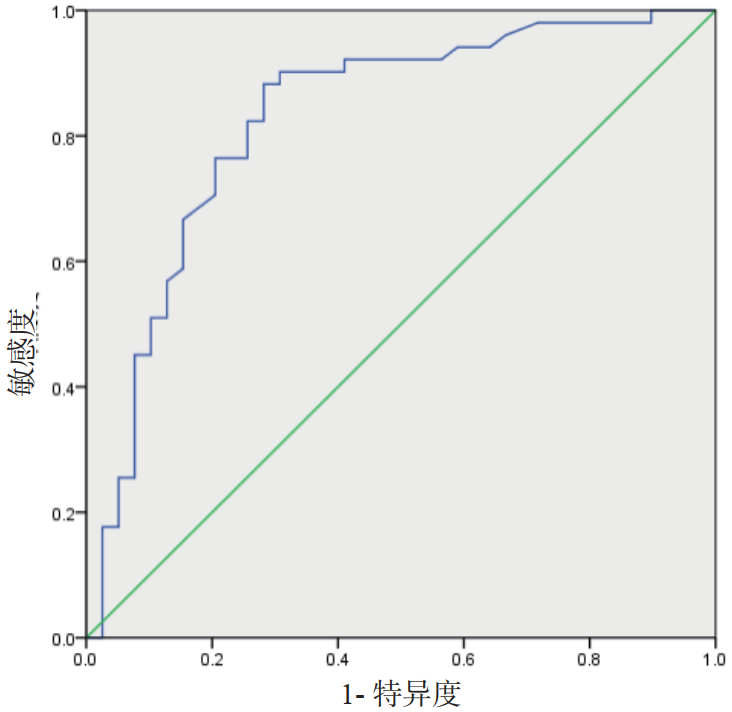

| 图 3 超声测量CSA对喂养不耐受预测的ROC曲线 Fig 3 ROC curve of CSA measured by ultrasound |

构建超声治疗组前3 d的CSA对喂养不耐受预测的ROC曲线。AUC为0.828,95% CI为0.737~0.919,其预测喂养不耐受的最佳截断值为7.835 cm2,其预测敏感度为88.20%,特异度为71.80%。

本研究立足于以上理论指导,采用床旁超声测量胃窦横截面积来指导脓毒症患者的早期个体化肠内营养方案的制定实施。结果发现,经床旁超声连续监测患者胃肠功能,能够在较早期地发现患者的喂养不耐受情况,超声治疗组在第1天发现喂养不耐受的发生率(36.67%)显著高于常规治疗组(10.00%),并制定个体化的治疗方案,入院第3天超声治疗组的喂养不耐受发生率仅为10.00%,显著低于常规治疗组(40.00%)。治疗至第5天,超声治疗组的相关功能评分、营养状态指标及炎症相关指标等较入院时均显著改善,且显著优于常规治疗组,另外超声治疗组患者的ICU住院天数及误吸发生率更低。各项指标均提示床旁超声测量CSA指导脓毒症患者的早期个体化肠内营养方案实施的有效性。为进一步探究CSA对喂养不耐受的预测价值,首先对CSA与传统功能评分系统及指标进行了相关性分析,其相关系数的绝对值均在0.6以上,其中与胃肠功能障碍评分、腹内压的相关性高达0.79、0.71。接着ROC曲线也显示CSA预测喂养不耐受的AUC为0.828,其敏感度和特异度分别为88.20%和71.80%,其预测的Cut off值为7.835 cm2。虽然其敏感度高达90%左右,但其特异度为70.00%左右,阴性排除率相对偏低,这也提示我们可能需要结合患者临床表现综合评定。